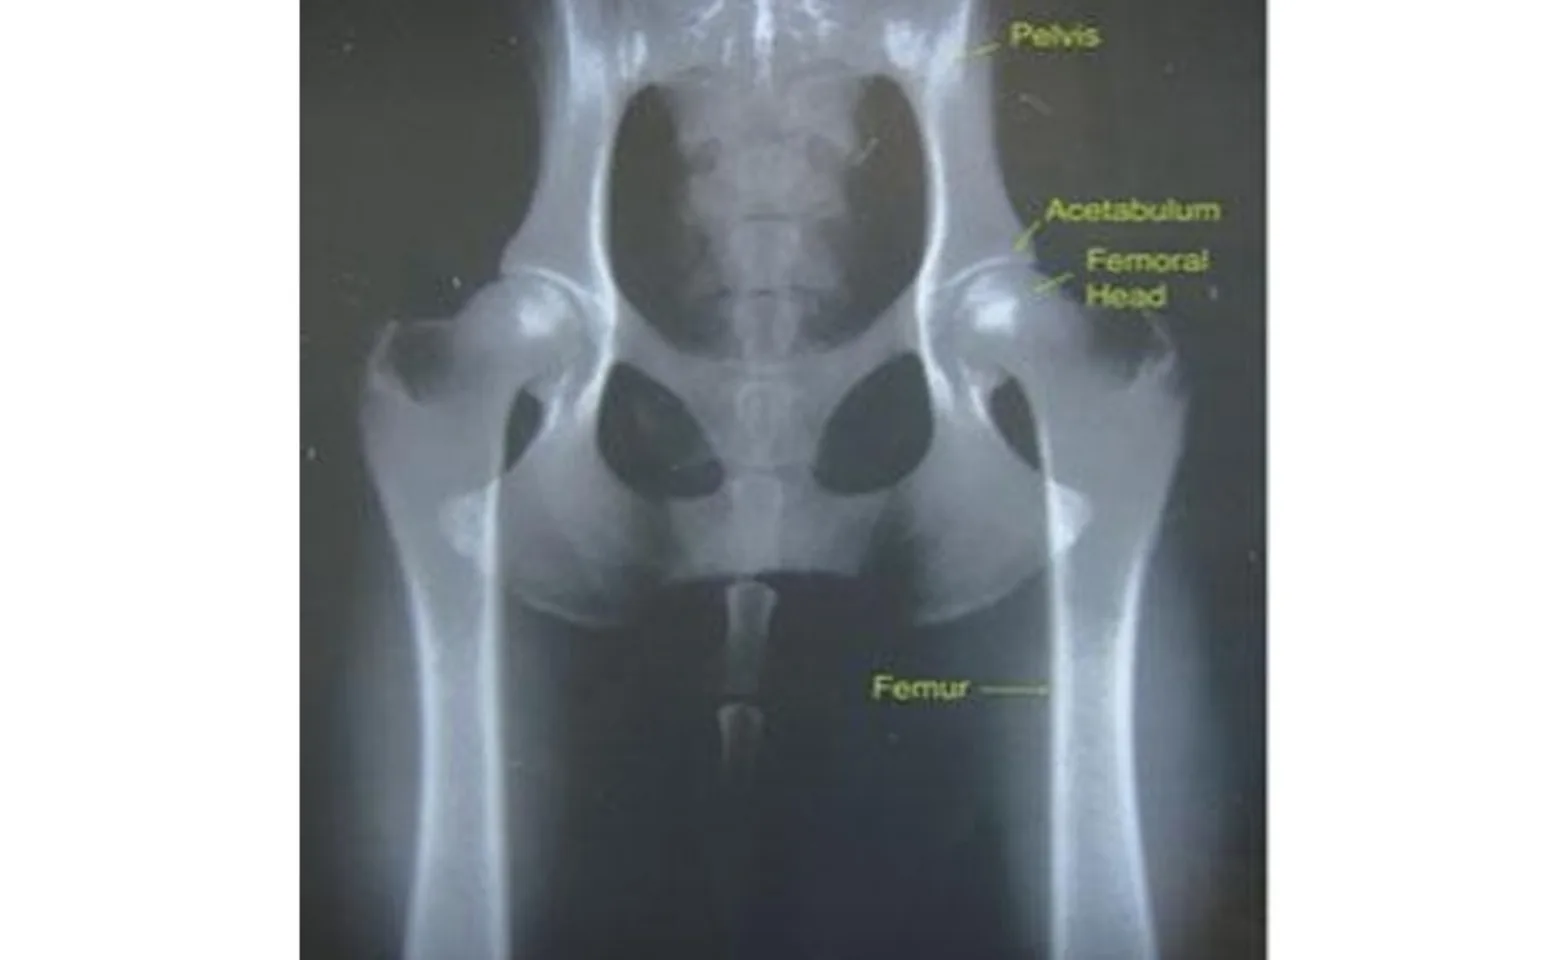

The canine hip is a “ball and socket” joint between the pelvis and the femur. The head of the femur makes up the ball part of the joint, which articulates with the acetabulum (cup) within the pelvis (Figure 1). The head of the femur and the acetabulum are held together by various soft tissue structures, including the joint capsule, ligaments, tendons, and surrounding musculature. In hip dysplasia, the femoral head and acetabulum do not t together perfectly, causing instability of the joint. The instability leads to inflammation and remodeling of cartilage and bone associated with the joint, which in turn leads to irreversible arthritis.

Figure 1: Normal canine hips with important anatomical features highlighted.

Radiography (X-ray) is the principle method for diagnosing hip dysplasia in veterinary patients. A normal canine hip radiograph is shown in Figure 1. Note the round femoral heads that are seated within deep round sockets (acetabulum). There is no evidence of separation of the joint or arthritis.